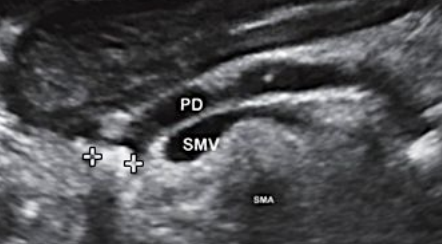

Describe this image

US guided FNA of a pancreatic tumor located in the head of the pancreas (based on landmarks)

Dx?

An EUS image of a well-defined, hypoechoic cyst with a “central star” and microcysts/septations.

Dx: benign serous cystadenoma